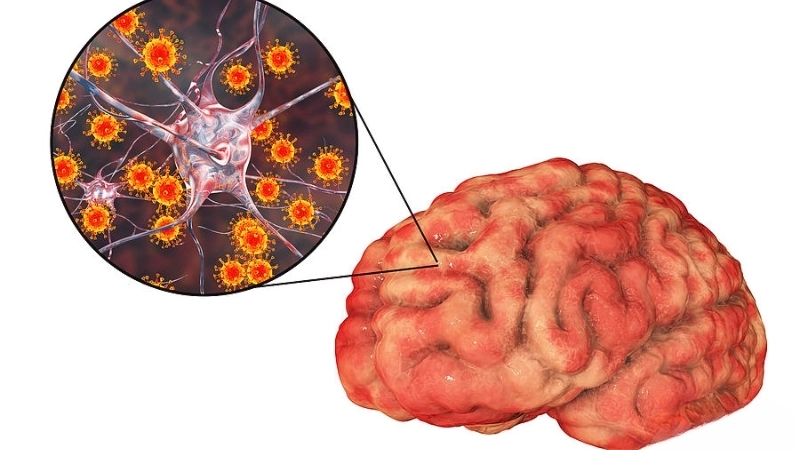

Image description of Viral Encephalitis

Viral encephalitis is a serious condition where a viral infection causes inflammation in the brain. It can range from mild to life-threatening, requiring early detection and treatment.